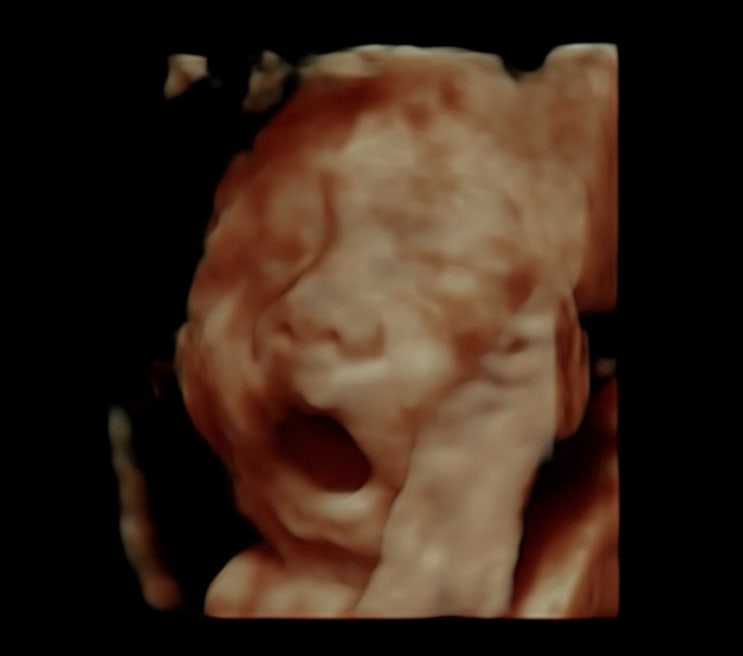

[임신기록] 25주 - 27주

> 1204 (25w1d) -꿀비 첫 딸꾹질 > 1210 (26w) - 26주 입체초음파 > 1212 (26w2d) - 지난 주말 차...